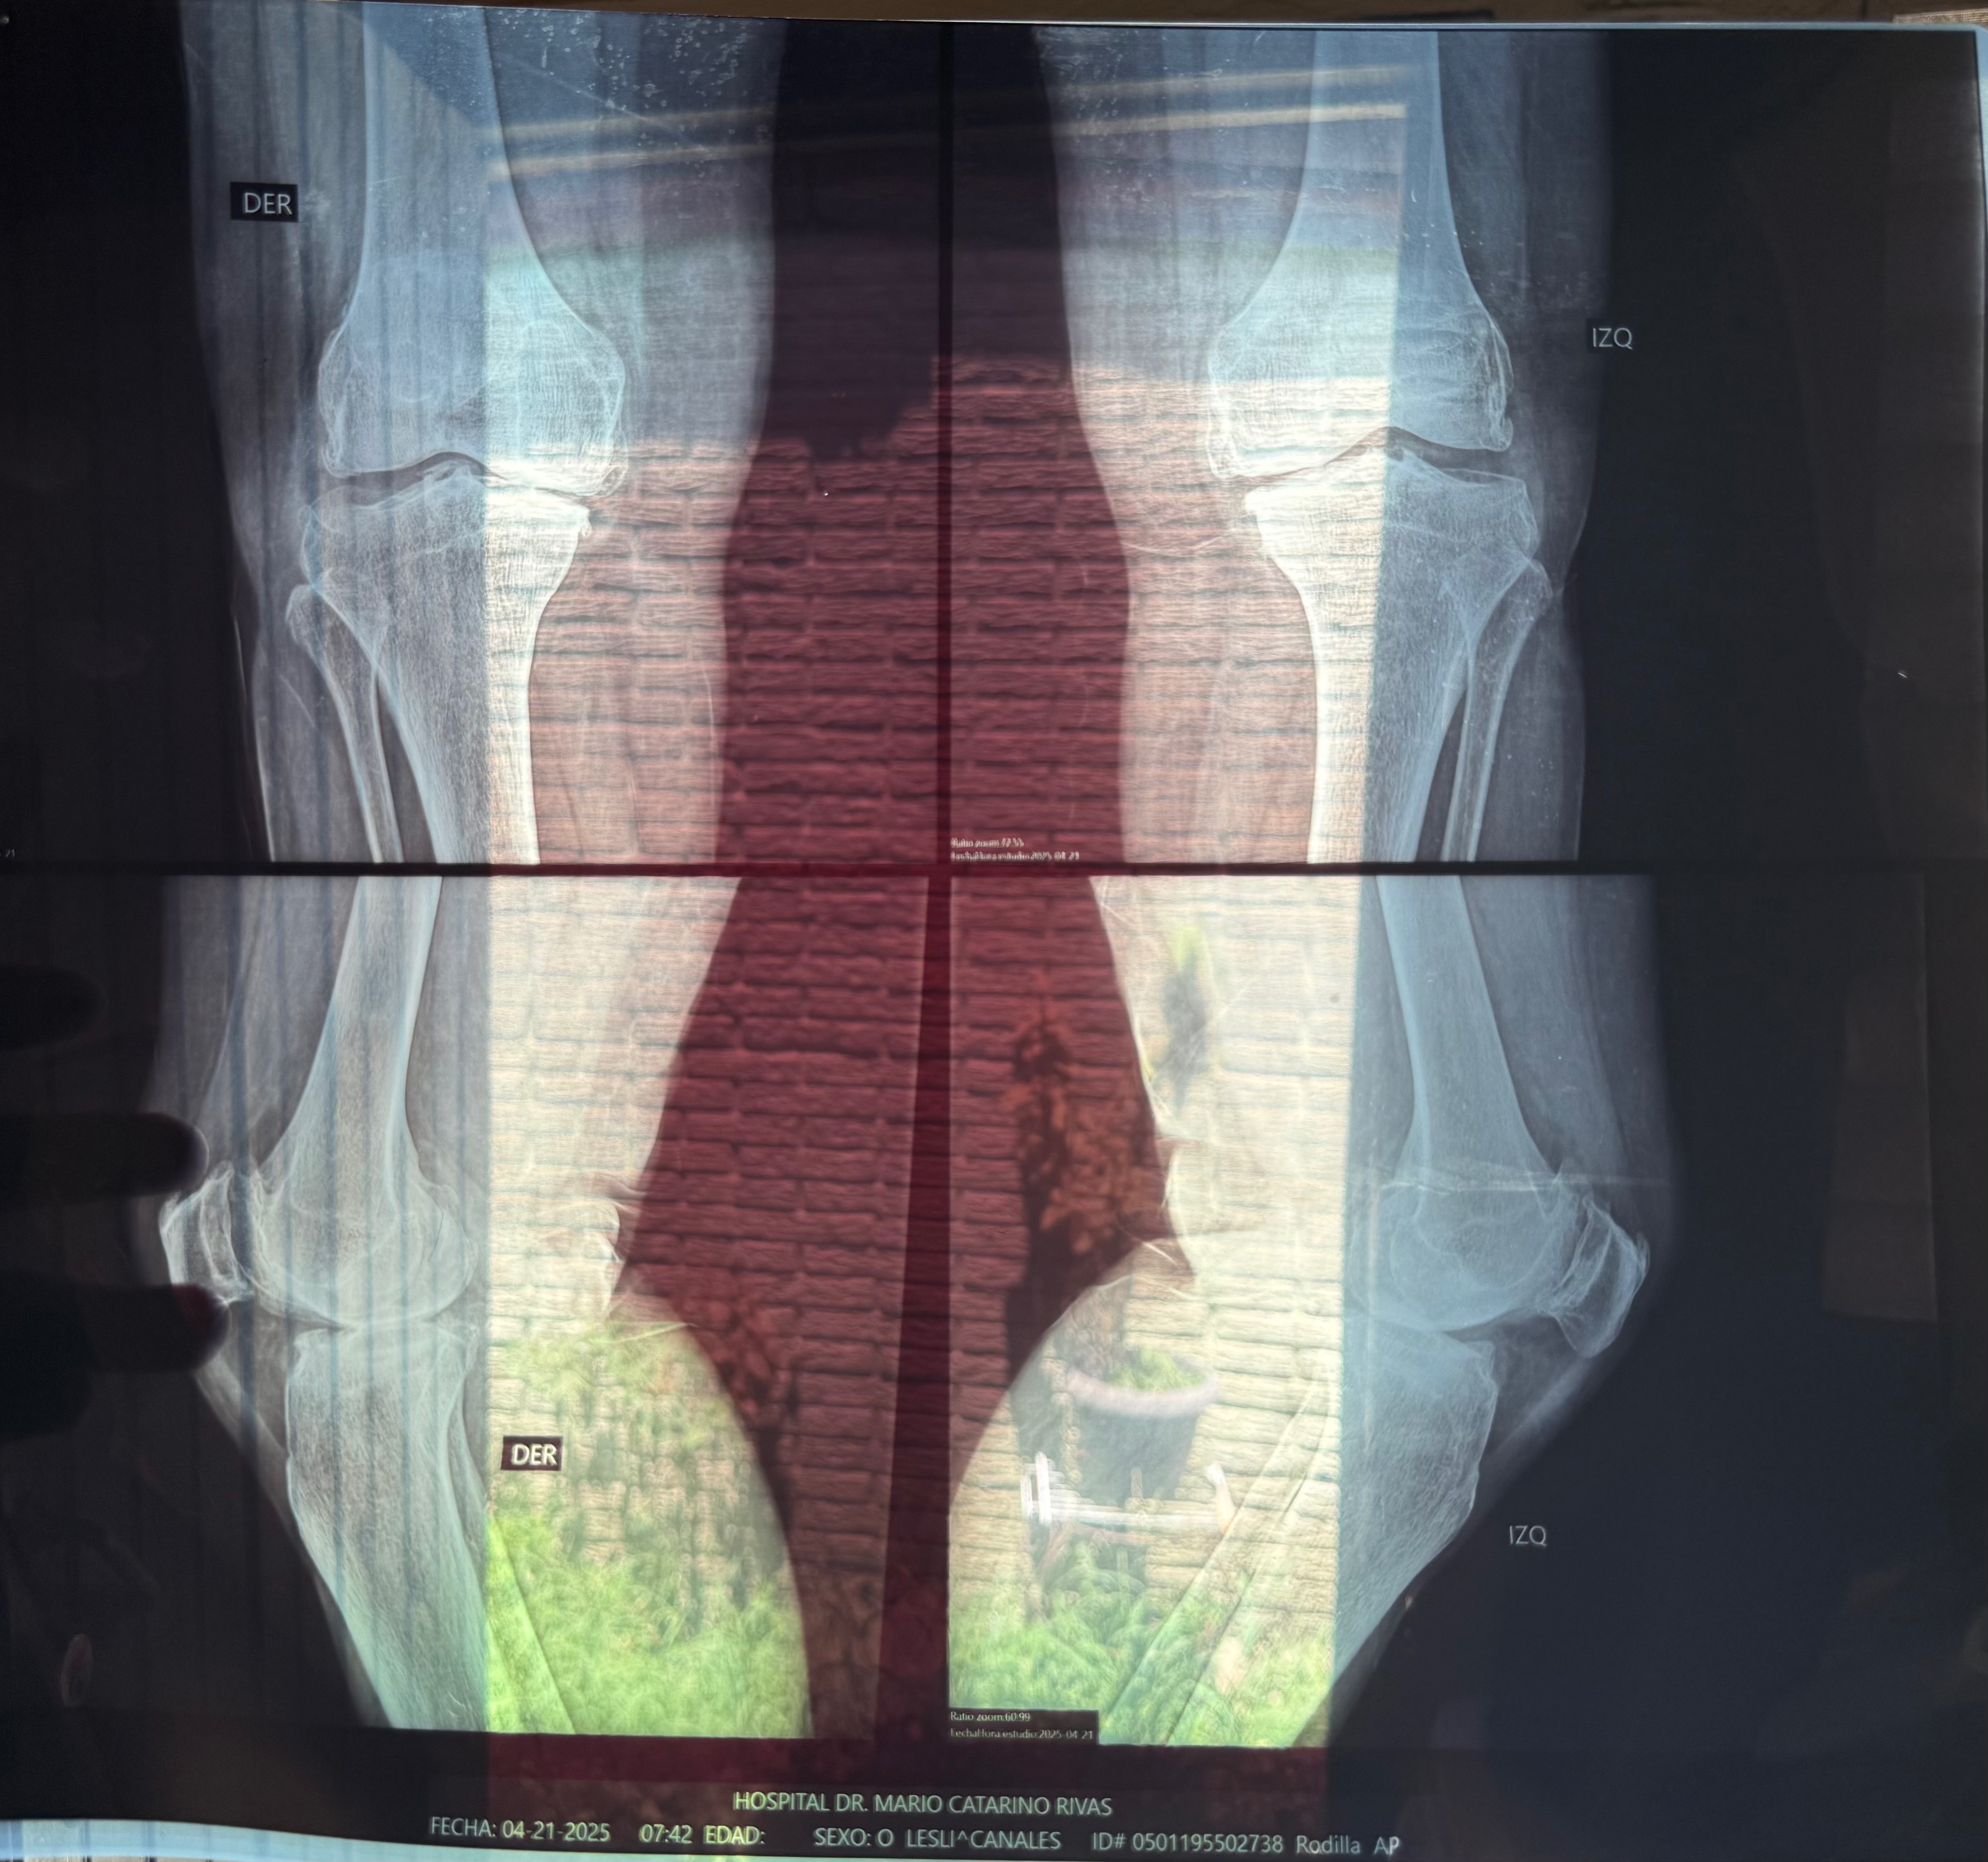

After many medical consultations, the diagnosis is clear: I urgently need total knee replacement surgery on both knees. Unfortunately, the cost of the prosthetic implants and the surgery itself is far beyond what I can afford.

Tras múltiples evaluaciones médicas, el diagnóstico es claro: necesito una cirugía de reemplazo total de ambas rodillas con carácter urgente. Sin embargo, el costo de las prótesis y del procedimiento quirúrgico es elevado y, lamentablemente, está fuera de mis posibilidades económicas.